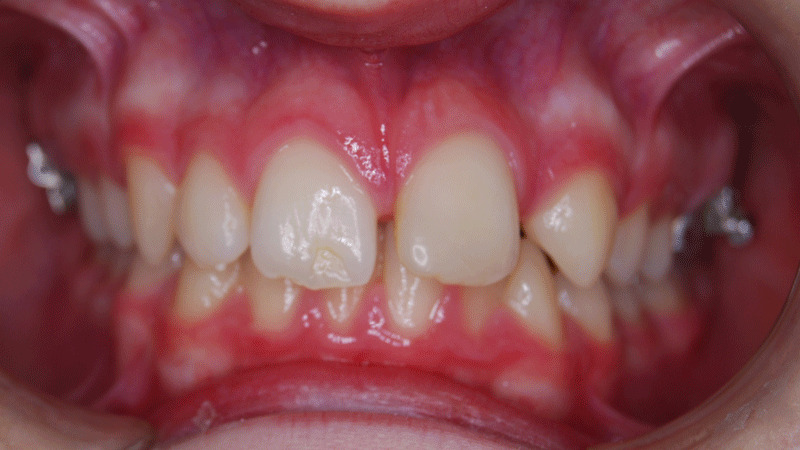

Cuando los dientes delanteros superiores ocluyen excesivamente sobre los inferiores hablamos de sobremordida o mordida profunda. Es aconsejable que esta maloclusión se trate de forma temprana en niños y jóvenes.

La sobremordida, lo que coloquialmente se conoce como mordida profunda, es un problema de maloclusión en que los dientes de arriba están adelantados y cubren excesivamente a los inferiores. Por lo tanto, podemos afirmar que existen distintos grados de sobremordida.

El overbite o sobremordida es la distancia entre el borde del incisivo central superior e inferior en sentido vertical. El overbite considerado normal tiene el incisivo superior sobrepasando aproximadamente 1/3 al incisivo inferior.

Cuando la mordida profunda alcanza un grado máximo, es decir, cuando los incisivos centrales superiores cubren completamente a los inferiores, hablamos de sobremordida severa. En ocasiones, también es conocida como sobremordida aumentada.